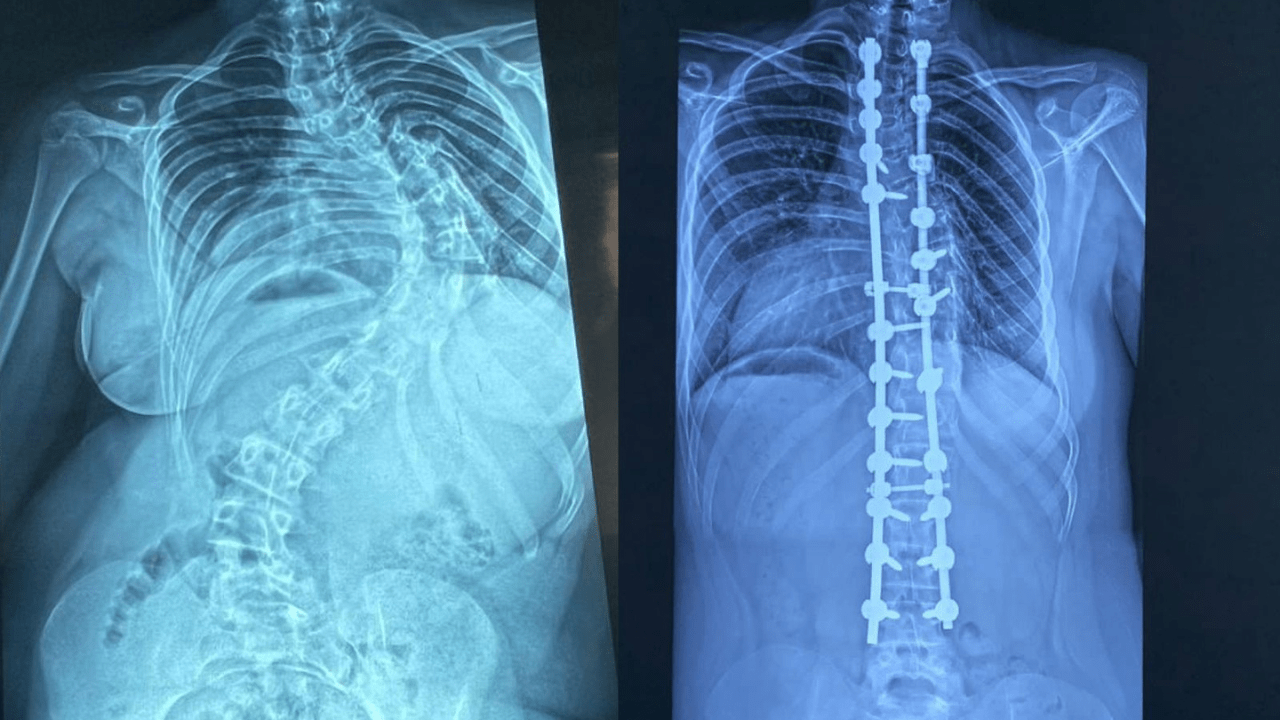

La escoliosis es una desviación de la columna vertebral mayor de 15 grados. El especialista detalló que la forma más frecuente es la idiopática del adolescente.

Indicó que existen diferentes tipos de la enfermedad: congénitas (cuando el paciente nace con la condición), asociadas a patologías de base como las neuromusculares y la más común, la idiopática del adolescente.

Advirtió que, cuando progresa, puede comprometer órganos vitales.

“Es una patología que básicamente va a mermar la calidad de vida de los pacientes, porque esas desviaciones que continúan progresando durante el crecimiento pueden comprimir órganos internos como el corazón y los pulmones”, explicó.

Sobre los resultados, destacó que muchos pacientes intervenidos hoy llevan una vida normal.

“Después de una cirugía como esta pueden hacer su vida prácticamente normal, en igualdad de condiciones que cualquier otro niño”.